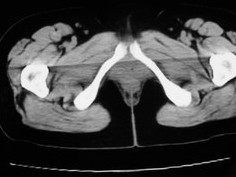

女42岁肛门下坠感4月余.

子宫轻度右倾,体后方见小似新月形低密度区,边界清楚。余所见无明显异常。

考虑:子宫直肠窝少量积液(盆腔炎所致)。

子宫轻度右倾,体后方见小似新月形低密度区,道格拉斯窝周围间隙欠清晰,有索条模糊影阴,多考虑:肛周脓肿可能性大。

肛周脓肿临床症状比较典型,此患者:女42岁肛门下坠感4月余,与其不符

子宫轻度右倾,体后方见小似新月形低密度区,道格拉斯窝周围间隙欠清晰,有索条模糊影阴,多考虑:肛周慢性感染可能。